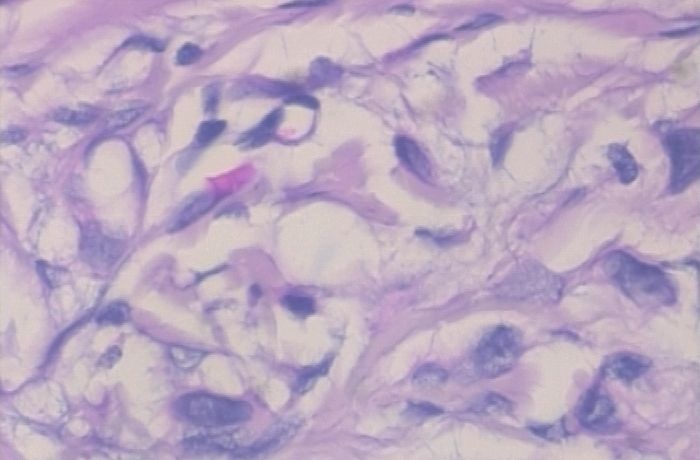

以上两张图片是良性样本